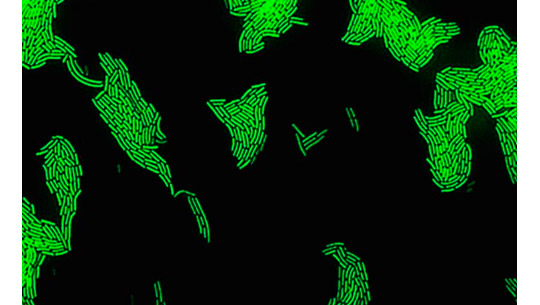

Bacterias que recién emergen del estado «caótico» recién descubierto, en un laboratorio de la Universidad Hebrea.

(Universidad Hebrea / Orit Gefen / Yoav Kaplan)